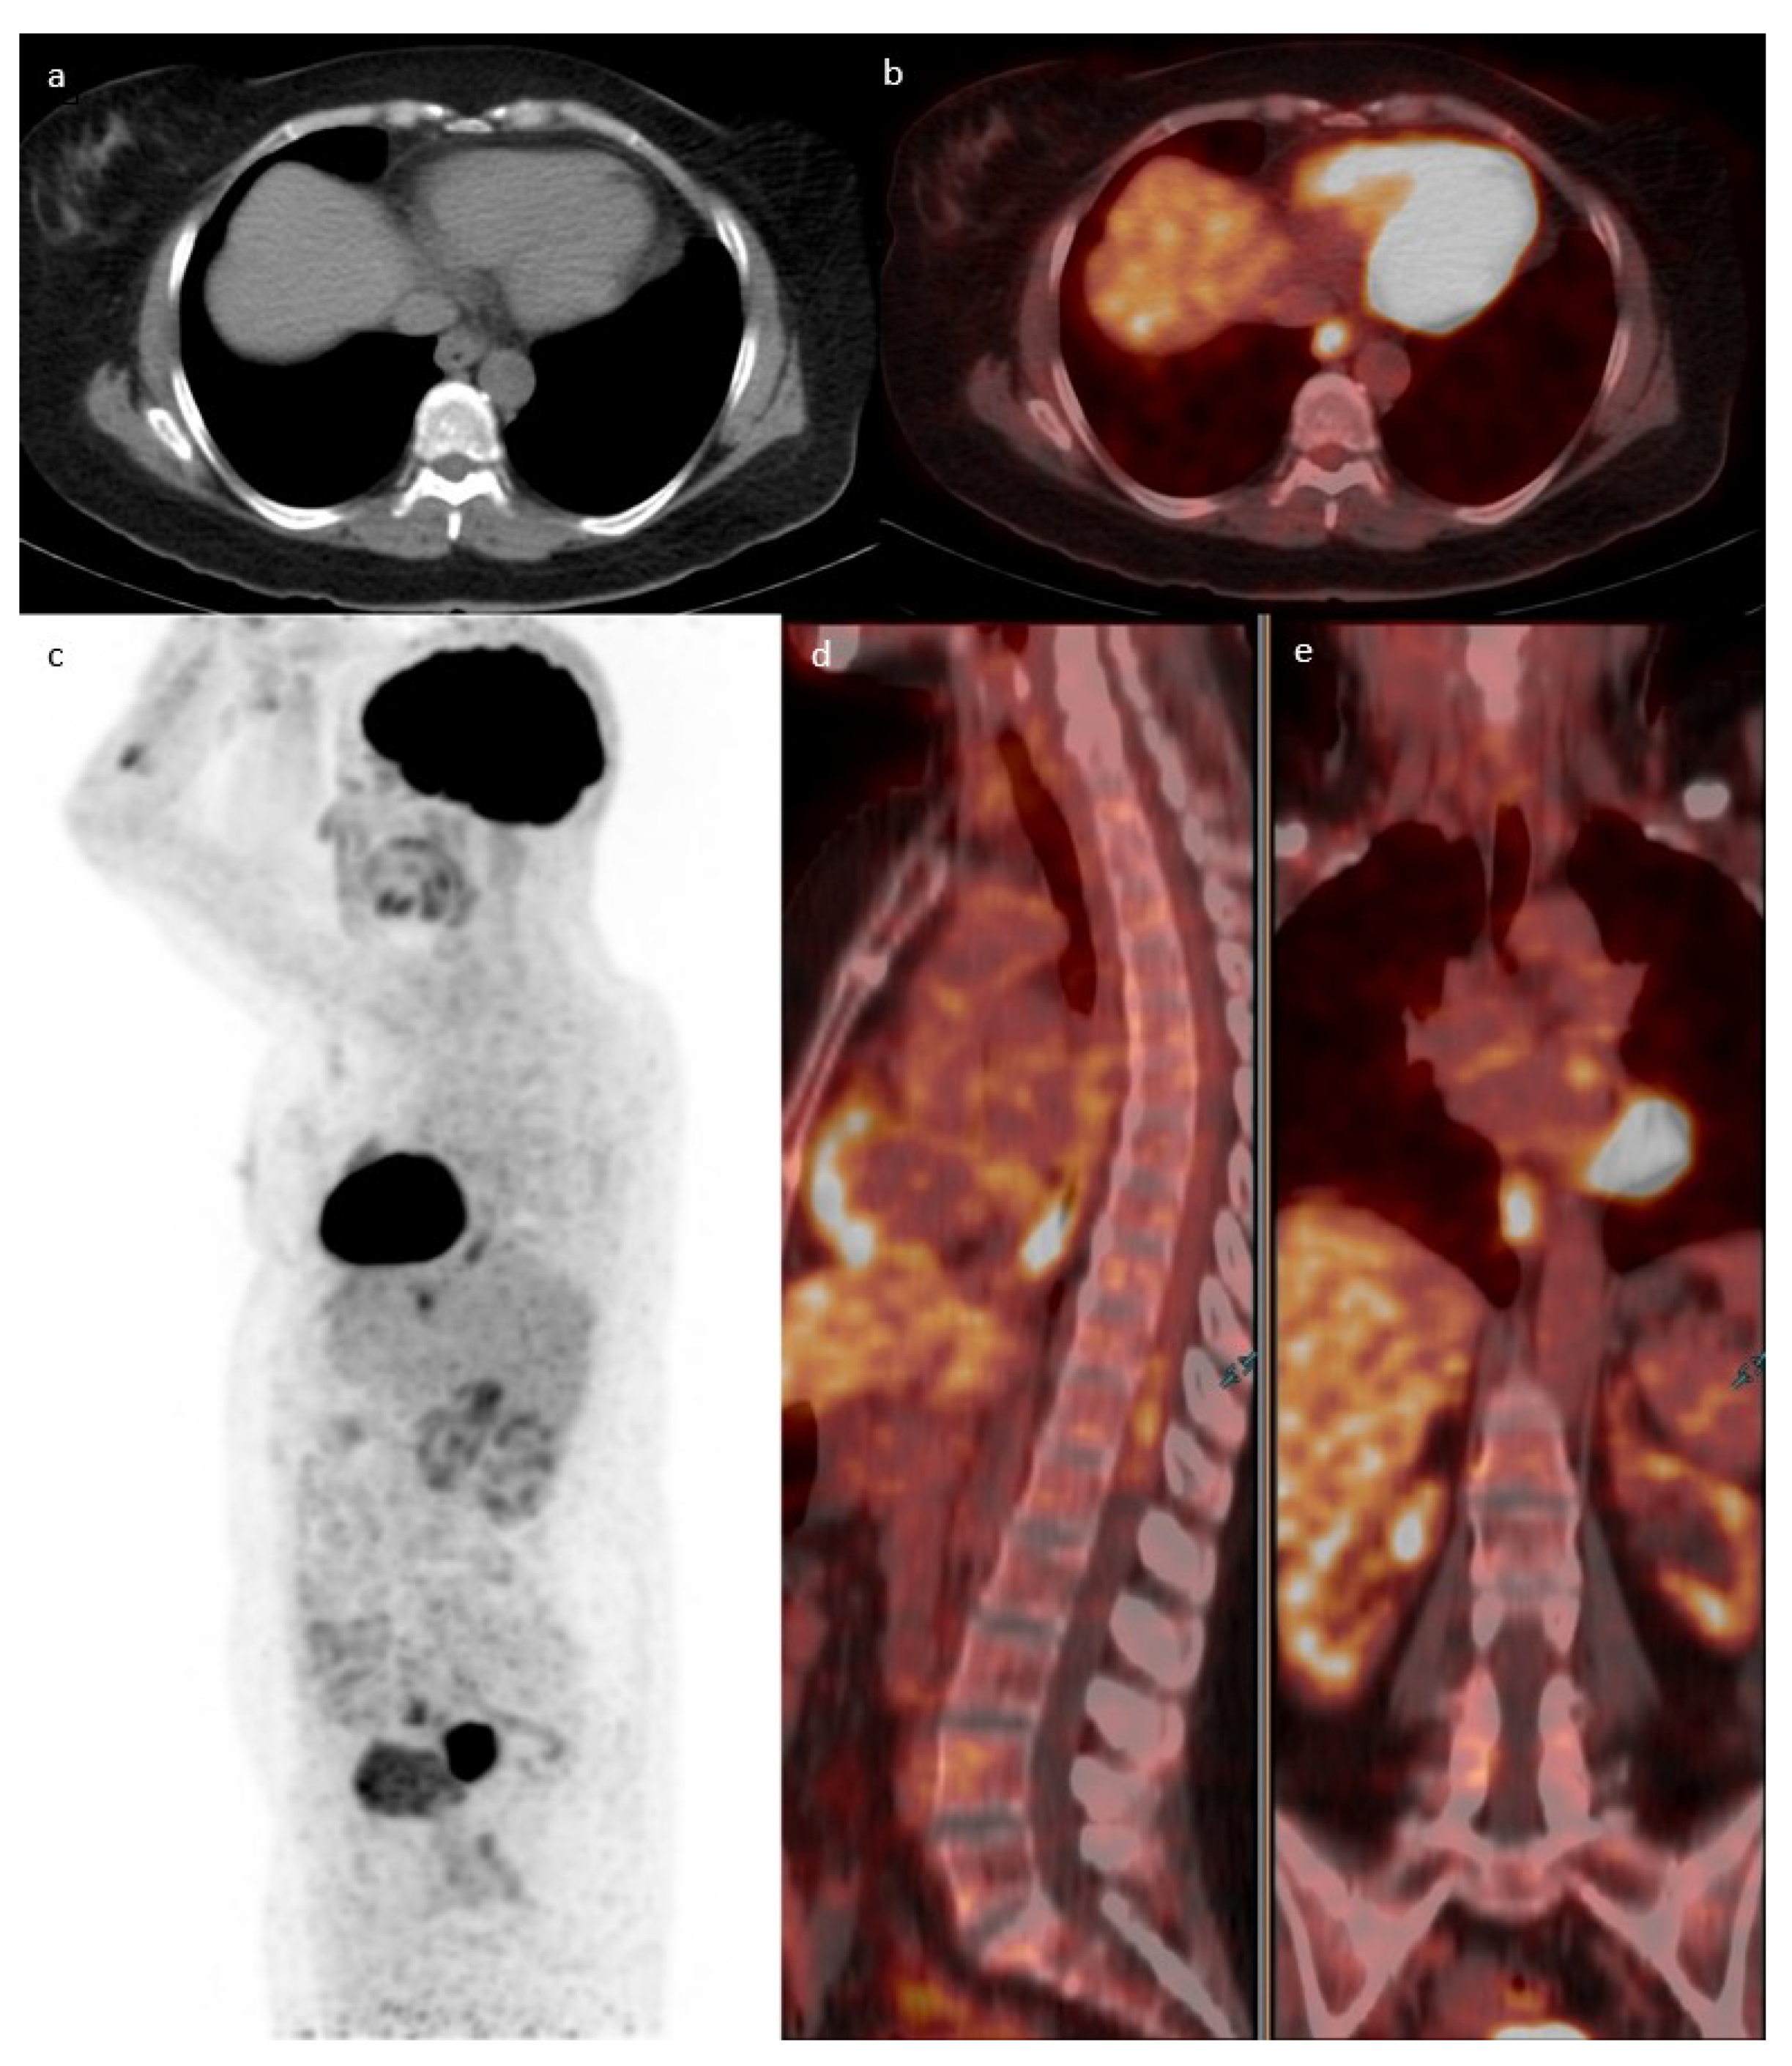

On pathologic examination, of the sixteen detected carcinomas, twelve were biopsied from a mass while the other four were detected on pathology (absence of a mass on endoscopy). Of the sixteen detected carcinomas, seven were in the stomach and one was detected in the jejunum while the remaining eight were present in the colon. One example is presented in Figure 3. Patients with incidental upper GIT malignancy were younger than the studied population (53 ± 17.6 compared to 64.6 ± 16 years). All malignancies in the lower GIT showed focal uptake, while 5/8 (62.5%) in the upper GIT had focal uptake. The remaining 3/8 (37.5%) malignancies were detected as diffuse uptake in the upper GIT. The characteristics of all detected cancer/pre-cancer lesions are summarized in Table 5 and Table 6.

Figure 3. Case of a 71-year-old male known to have primary bladder cancer. Axial cuts of CT (a) fused with PET (b) showing a focus of increased uptake in the lower rectum (SUVmax 19.1) with corresponding circumferential wall thickening suspicious for malignancy. This lesion is redemonstrated in the MIP (c), sagittal (d), and coronal PET/CT cuts (e). Rectal biopsy confirmed the diagnosis of moderately differentiated adenocarcinoma.